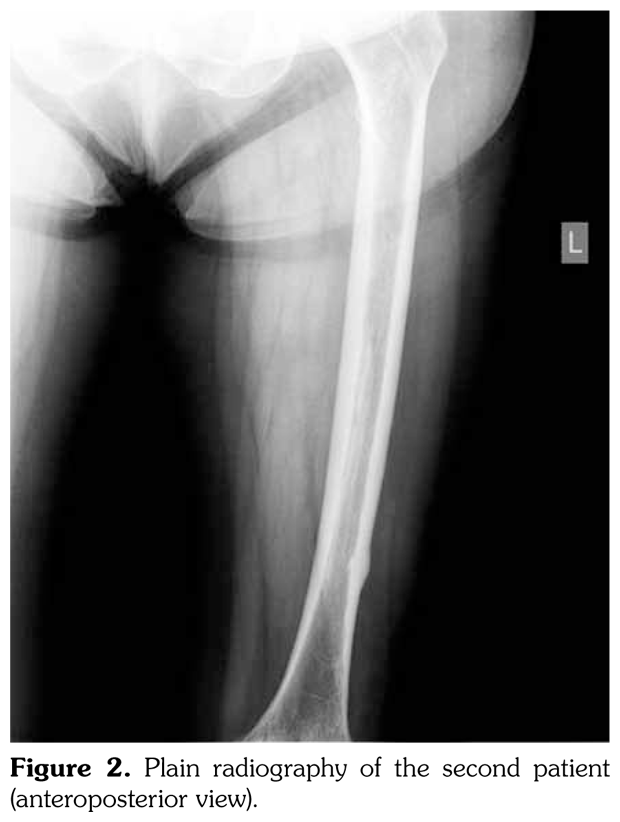

Case 2– A 61-year-old female patient presented with anterior thigh pain and difficulty in walking. Pain severity was 7 over 10 point according to visual analog scale. She had been treated with alendronate 70 mg per week with calcium plus vitamin D for two years. Plain radiographs of femur were taken upon clinical presentation. Cortical stress reaction was detected in both femoral shafts on plain radiographs (Figure 2). Computed tomographic imaging was performed to rule out fracture (Figure 3). Bone scintigraphy showed increased uptake in distal (1)/3 ends of femoral shafts (Figure 4). Serum calcium value was normal and urinary deoxypiridinoline level was mildly increased (46 nM/mMCre).

Bone scintigraphy of the patients revealed increased uptake in femoral diaphysis. Atypical bisphosphonate associated subtrochanteric and femoral shaft stress fractures show specific appearance on bone scintigraphy characterized by mild uptake in multifocal endosteal thickening of the lateral femoral diaphysis.(11)